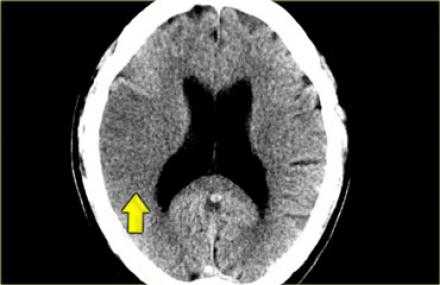

Симптом плотной СМА.

Данный симптом проявляется в следствии тромбирования или эмболизации СМА. У ниже представленного пациента симптом плотной СМА. На КТ ангиография визуализируется окклюзия СМА.